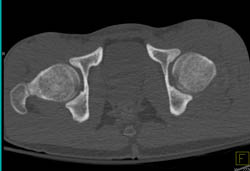

Dislocation of Hip in 3D With Disarticulation